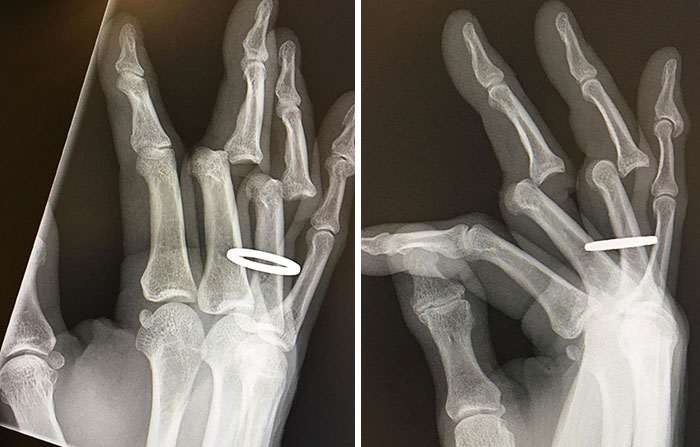

Рентгеновские снимки поломанных пальцев после аварии